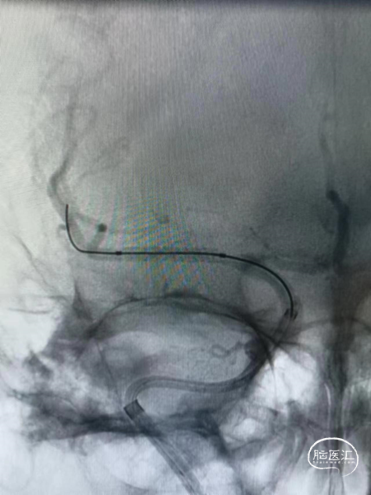

术后正位造影。

术后侧位造影